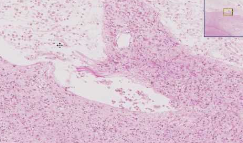

- 컴퓨터 단층 촬영(CT) 스캔: 뇌출혈 여부를 빠르게 확인하고, 뇌경색의 위치와 크기를 파악합니다.

- 자기 공명 영상(MRI): 더 정밀하게 뇌 구조를 확인하여 뇌경색의 유형과 위치를 결정하는 데 사용됩니다.